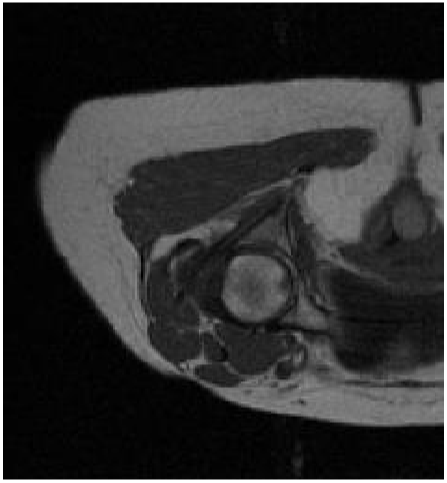

LOW-RES AXIAL ANKLE